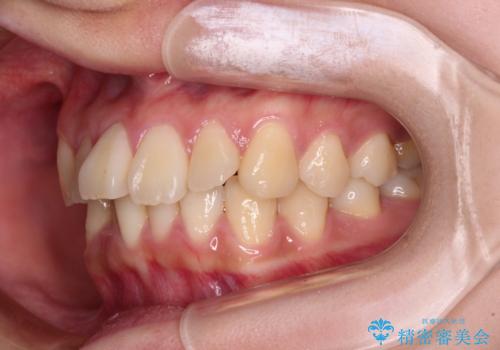

- 前歯の捻れを気にして来院された患者様です。

上顎前歯が捻れて前方に飛び出しており、下顎前歯もそれに沿うようにデコボコとなっていました。

IPR(歯と歯の間を削る処置)によりスペースを獲得して下顎前歯のデコボコを改善し、上顎前歯は下顎前歯と接する位置にまで引っ込めるように設定し、インビザラインにて矯正治療を行うこととしました。